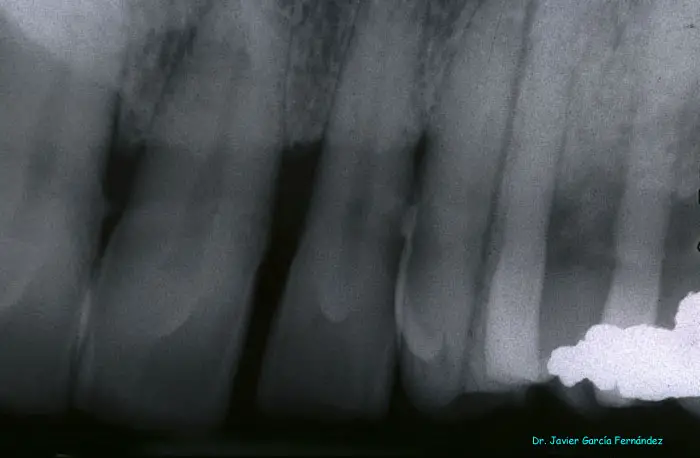

image027